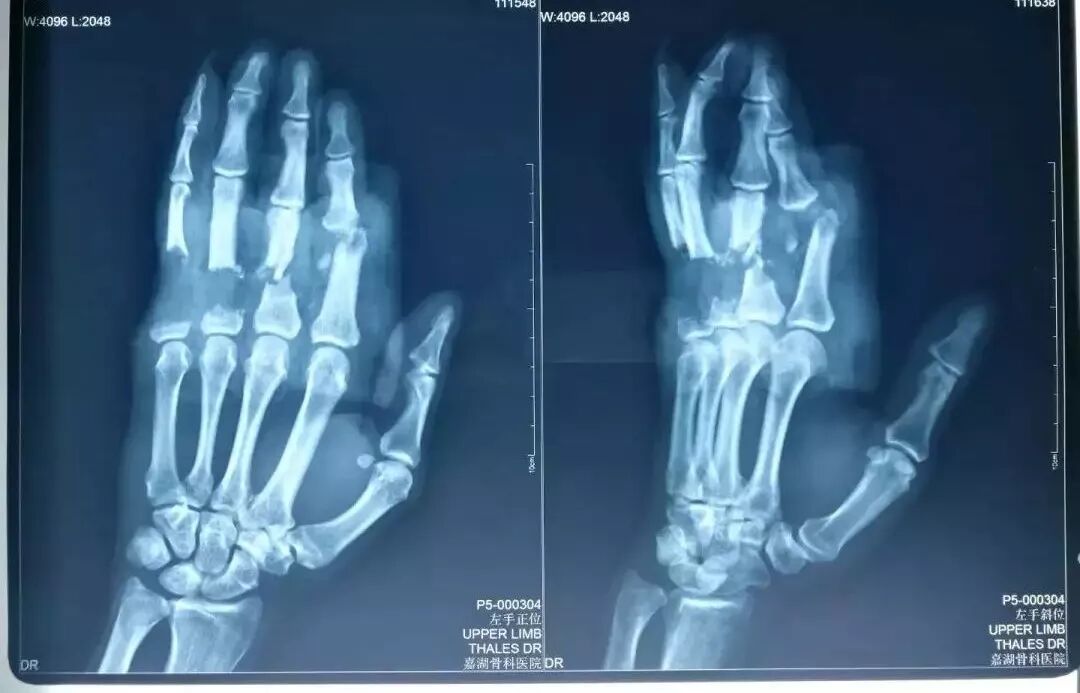

門診第一時(shí)間給予拍X線片準(zhǔn)確掌握傷情,醫(yī)生發(fā)現(xiàn),老閔左手2-4指近節(jié)指骨分離骨折,大部分?jǐn)嗔?,僅剩背側(cè)少許挫傷表皮相連,指骨斷面還呈現(xiàn)破碎狀,骨質(zhì)缺損,指間關(guān)節(jié)脫位,關(guān)節(jié)面缺損并外露,另外還存在屈、伸肌腱斷裂,肌腱斷端回縮,斷指無血運(yùn)及感覺,顏色蒼白,毛細(xì)血管反應(yīng)無,各指傷口皮緣破碎……傷情可謂十分慘烈。

手術(shù)前